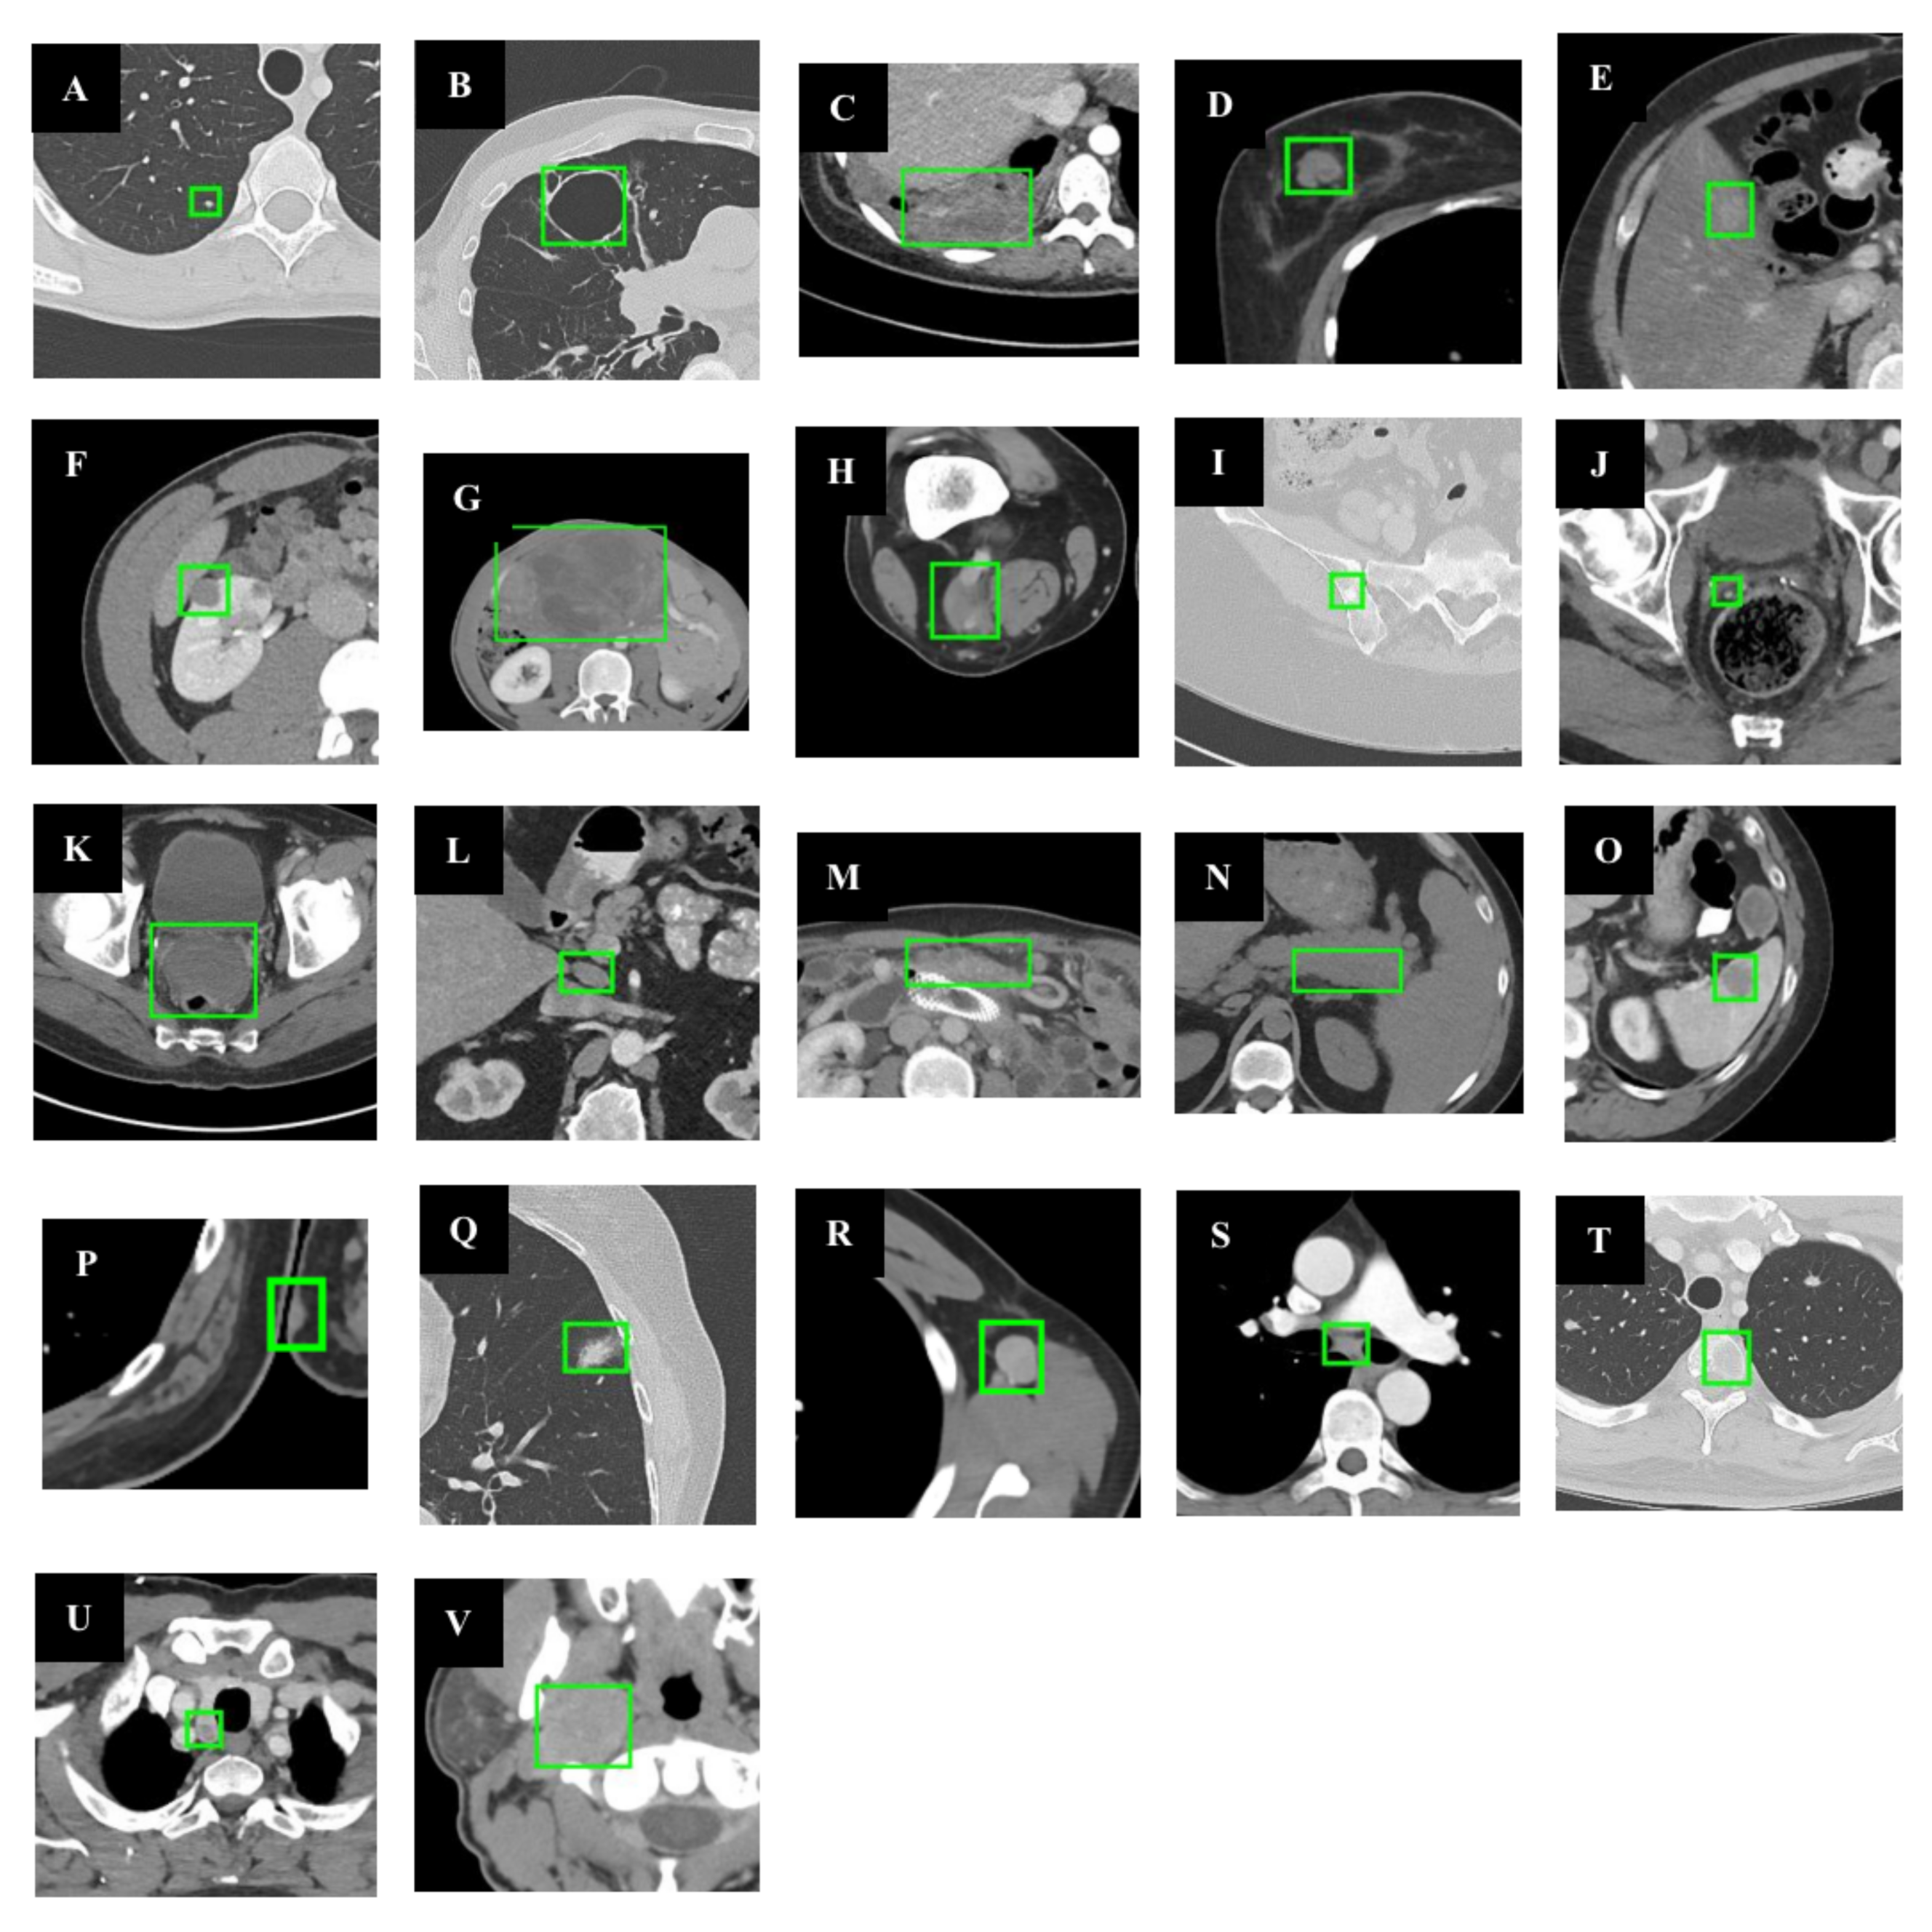

Figure 3.

Illustration of different data augmentation methods. (A) series-Mixup; (B) Random-erase; (C) CutMix; (D) Mosaic; (E) source images.